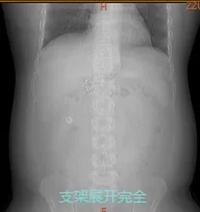

近日,消化内科二病区刘谦主任团队完成了医院首例胃转流支架系统置入术,全程仅耗时15分钟,过程顺利,术后患者支架展开良好,住院3天后便康复出院。